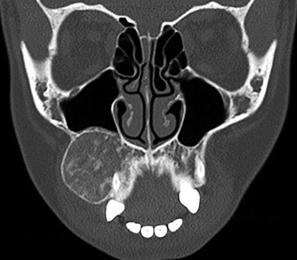

chondroma

synovial chondromatosis